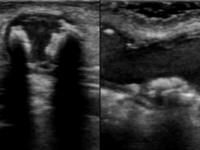

石灰化画像

吻合部画像

・吻合部の観察

吻合形態や、石灰化の有無、狭窄等を観察しています。